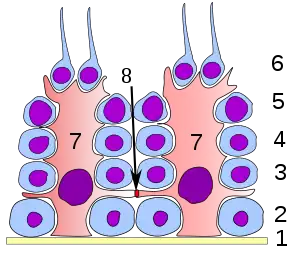

Les virus infectent généralement les cellules en y entrant via une endocytose médiée par un récepteur auquel chaque virus doit d'abord se lier. Le récepteur utilisé par le SARS-CoV-2 est une protéine de surface cellulaire : l'enzyme de conversion de l'angiotensine 2 (ACE2), la même que pour le SARS-CoV mais avec une affinité 10 à 20 fois plus importante que le SARS-CoV[63]. Le virus se lie avec le récepteur ACE2 par ses protéines présentes dans les épines (spicules) de sa couronne (protein spike)[63].

L'ACE2 est une enzyme de conversion des récepteurs cellulaires de l'angiotensine II[64]. Elle est présente sur les « cellules épithéliales alvéolaires AT2 » situées dans les alvéoles pulmonaires, mais aussi dans l'œsophage (dans les cellules épithéliales supérieures et stratifiées), dans les entérocytes absorbants de l'iléon et du côlon[64],[65] et dans le pancréas (de légères pancréatites sont d'ailleurs observées, via analyses d'amylase et de lipase et via l'imagerie médicale, chez les malades légèrement ou sévèrement atteints par la Covid-19[65]). Les « cellules à AT2 » sont connues pour être sujettes aux infections virales[66].

Les lymphocytes cytotoxiques sont chargés de détruire les cellules dans lesquelles un virus commence à se répliquer : ce sont d'abord les cellules tueuses naturelles (éléments de l'immunité innée), et les lymphocytes T cytotoxiques qui viennent compléter le travail des précédentes et le poursuivre dans la durée. Ces cellules du système immunitaire permettent de bloquer en quelques heures ou quelques jours une infection virale en cours[69].

Une équipe médicale chinoise[70] constate qu'au début de la maladie, l'organisme des patients (panel de 68 malades, âge médian de 47 ans) n'arrive pas à produire les cellules NK et les lymphocytes T CD8+ nécessaires pour combattre le virus. Le nombre moyen de ces cellules a même chuté sous la moyenne normale[70]. Ceci a été révélé par le suivi des niveaux d'expression du récepteur NKG2A, « récepteur inhibiteur » déjà connu comme indicateur d'« épuisement » de ces types cellulaires lors d'autres infections virales chroniques[70]. Et, le jour de leur admission, la leucocytose et la lymphopénie des patients est proportionnelle à la gravité de la maladie[70] (atteignant surtout les LT CD8+). Autrement dit : la phase de progression du virus dans les cas sévères de Covid-19 correspondait à un « épuisement fonctionnel des lymphocytes cytotoxiques », avec un nombre total de cellules tueuses naturelles et de LT CD8+ qui s'effondrait quand le SARS-CoV-2 se développait, alors que l'expression de NKG2A augmentait[70]. Par contre, chez les convalescents, on voyait le nombre de cellules tueuses NK et de LT CD8+ se restaurer, pendant que l'expression de NKG2A diminuait[70]. Ceci laisse penser que dans les cas les plus graves, le SARS-CoV-2 peut bloquer précocement, efficacement (et durablement) notre immunité antivirale. Les auteurs de l'article estiment que le récepteur NKG2A pourrait être une cible thérapeutique à étudier[70].

Fin avril 2020, le virus a été détecté dans les cellules épithéliales alvéolaires de type II, les monocytes, les cellules épithéliales du tube digestif, les cellules tubulaires rénales distales, les cellules des glandes sudoripares cutanées, les éosinophiles parathyroïdes et hypophysaires, les cellules du cortex surrénalien, les cellules pariétales gastriques, les cellules pancréatiques, les cellules acineuses et les cellules de la glande séreuse trachéale. Différent du SARS-CoV-1, le SARS-CoV-2 a été principalement détecté dans les cellules épithéliales alvéolaires de type II et les macrophages pulmonaires, et en partie dans les ganglions lymphatiques hilaires, la rate et les testicules[78].

Fin octobre 2020, une prépublication américaine, encore à confirmer par les pairs, a recherché, parmi les cellules épithéliales, mésenchymateuses et immunitaires de la bouche, celles qui expriment le plus l’ACE2 (récepteur du virus) ; ce sont les glandes salivaires, la langue et les amygdales[79]. Les autopsies ont confirmé cette spécificité, qui pourrait expliquer que la Covid-19 induit non seulement une perte de l’odorat, mais aussi du goût et une sécheresse persistante de la bouche chez certains patients[79]. Un essai clinique a aussi conclu que les cellules épithéliales de la bouche peuvent effectivement être infectées par le SARS-CoV-2. Le taux de virus dans la salive des patients était positivement corrélé aux changements de goût et d’odeur ressentis. La dynamique d'excrétion virale était distincte pour les zones buccale et nasale et les patients en guérison ont présenté des anticorps salivaires contre les protéines du SARS-CoV-2[79]. Le SARS-CoV-2 installé dans les glandes salivaires pourrait contribuer à une prolongation ou évolution de la maladie, quand la salive infectée est avalée (induisant un risque d’infection intestinale) ou aspirée vers les poumons (avec alors un risque de pneumonie) ou expulsés lors des crachats, éternuements, postillons, d’une manière « peut-être sous-estimée » et parfois asymptomatique[79]. Ceci confirme, s'il en était besoin, l’enjeu du port du masque facial correctement ajusté et de la distanciation physique[79].